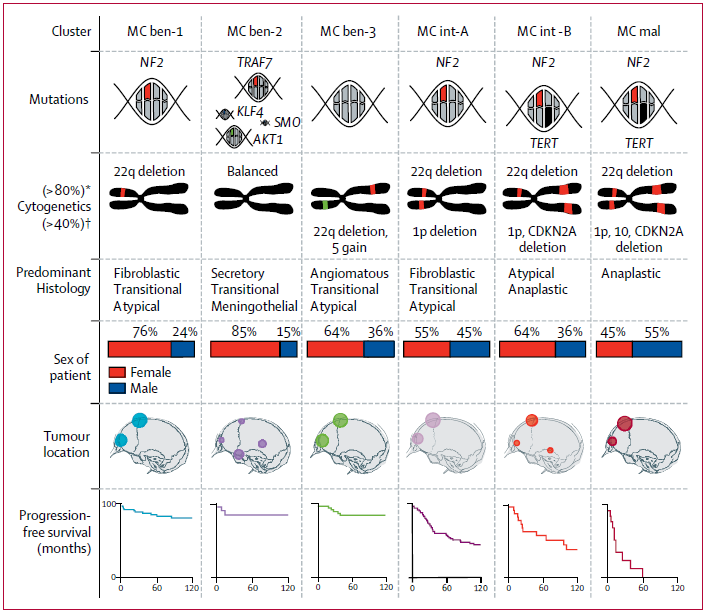

脑膜瘤分子分型:脑膜瘤是常见的颅内原发性脑肿瘤,当前脑肿瘤的诊断模式是组织型和基因型的整合诊断。虽然目前脑膜瘤的诊断仍然引用传统的组织分型,但是分子检测在脑膜瘤瘤诊断和预后评估中的作用越来越大,尤其是检测复发相关的分子标志物。关于脑膜瘤分子分型的研究越来越趋于成熟,近期在柳叶刀肿瘤学期刊中发表了脑膜瘤6亚型的分子分型研究,其中恶性脑膜瘤通常携带有NF2,TERT基因启动子激活突变,CDKN2A基因缺失,1p和10号染色体缺失等分子特征。

阔然精准诊疗脑肿瘤产品CaptioX-M是一款以NGS技术为基础的检测产品。CaptioX-M用于脑膜瘤的分子诊断,涵盖了脑膜瘤复发相关的67个基因(NF2、TERTp、CDKN2A/B、ARID1A和BIP1等)、预后相关的染色体(22q、1p、5、10等)拷贝数变异和潜在靶向治疗相关基因的信息,脑膜瘤CaptioX-M可用于脑膜瘤患者分子分型、预后评估和辅助医生制定治疗策略。